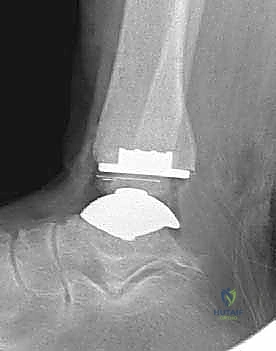

تتكون غرسة STAR من ثلاثة أجزاء رئيسية ولا تستخدم الأسمنت العظمي (Cementless)، بل تعتمد على النمو العظمي الدقيق داخل مسام الغرسة لتثبيتها بشكل دائم:

- المكون الظنبوبي (Tibial Component): صفيحة معدنية مسطحة من سبائك الكوبالت والكروم (Cobalt-Chromium)، تُثبت في أسفل عظمة الساق (الظنبوب) بواسطة أسطوانتين معدنيتين تدخلان في العظم لضمان الثبات المطلق.

- المكون الكاحلي (Talar Component): قطعة معدنية تغطي قبة عظم الكاحل، مصممة بشكل تشريحي منحني يحاكي تماماً شكل العظمة الأصلية، وتحتوي على أخدود طولي.

- الحشوة البلاستيكية المتحركة (Mobile Polyethylene Bearing): هذا هو سر نجاح غرسة STAR. هي قطعة من البلاستيك الطبي عالي الكثافة (UHMWPE) توضع بين القطعتين المعدنيتين. هذه القطعة ليست ثابتة، بل تنزلق بحرية للأمام والخلف، وتسمح بدرجة طفيفة من الدوران. هذا التصميم "المتحرك" يقلل بشكل هائل من إجهاد القص (Shear Stress) على واجهة العظم والمعدن، مما يقلل من احتمالية تخلخل الغرسة (Loosening) على المدى الطويل، ويمنح المريض نطاق حركة فسيولوجي مذهل.